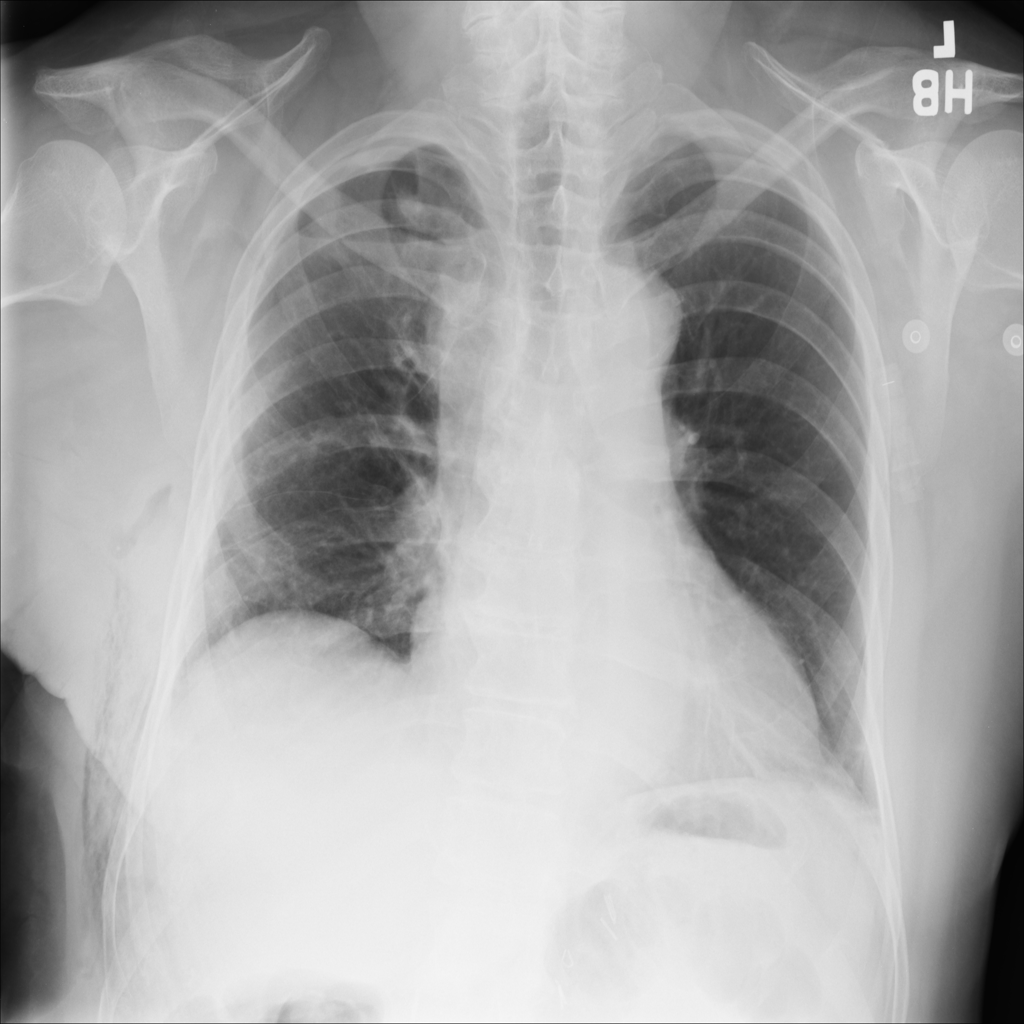

Showing up to 90 reference images for Emphysema.

PAT-B0DB · IMG-003Emphysema

PAT-B0DB · IMG-003

PA